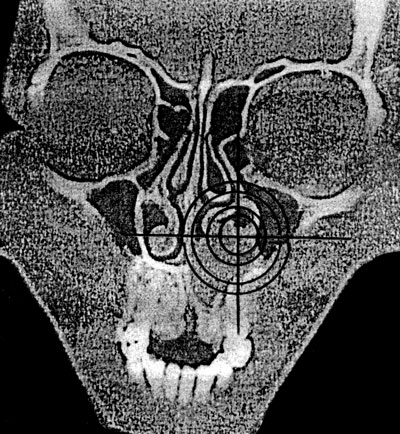

Оценка положения органа или его части может производиться как качественно, так и количественно (глубина залегания органа по кратчайшему расстоянию от поверхности, расчет координат с использованием осей абсцисс и ординат) – рис. 8.

Рис. 8. Определение координат кисты центрального отдела верхней челюсти (срез на уровне премоляров) на компьютерной томограмме (по: Соловьев М. М., Семенов Г. М., Галецкий Д. В., 2004).

Для реализации количественного подхода необходим выбор ориентации плоскости условного сечения и определение точки отсчета. К наиболее простым способам относится определение координат в горизонтальной плоскости с расположением «нулевой» точки в центре тела позвонка.